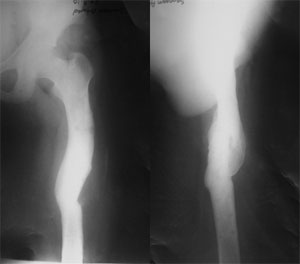

This 30 year old gentleman had met with an accident about 2 years back, following which there was a fracture of the left femur (thigh bone). He was treated at the local hospital where plating was done. The fracture healed and the plate was subsequently removed. He presented to us with deformity, shortening and awkward gait. The pictures here show the curvature in the thigh. The picture on the left shows an abnormal curvature of the thigh (red line) when we look from the front. The picture on the right shows the curvature of the thigh when we look from the side. Though it is a little proximal than normal, it is normal. |